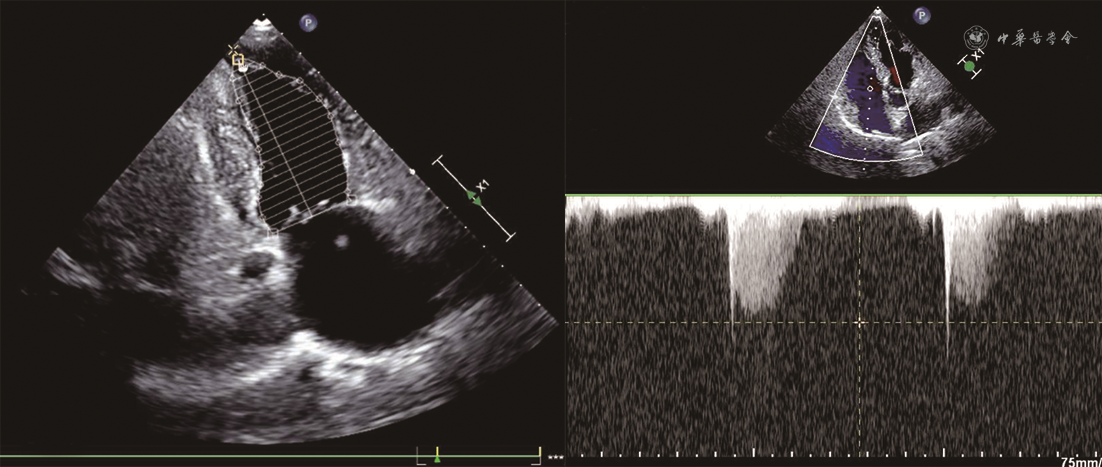

患者男,68岁,主因“胸痛、后背痛1 d”于2019年12月25日入院。患者有支气管哮喘病史,长期口服孟鲁司特。否认系统病史,否认食物、药物过敏史。无疫水、疫区接触史,无寄生虫接触史。入院体格检查:体温36.2 ℃,脉搏71次/min,呼吸25次/min,血压85/45 mmHg(1 mmHg=0.133 kPa)。神清语利,查体合作。浅表淋巴结未触及肿大。双肺呼吸音粗,可闻及肺底湿性啰音。心脏律齐,各瓣膜未闻及明显病理性杂音。腹软,无压痛及反跳痛。双下肢无水肿。血常规:白细胞计数22.39×109/L,嗜酸性粒细胞绝对值16.71×109/L[参考值(0.05~0.50)×109/L]。血浆D-二聚体1 027 μg/L(参考值<500 μg/L),肌钙蛋白T 2.950 μg/L,N末端B型利钠肽原9 949 ng/L(参考值0~1 800 ng/L),C反应蛋白1.32 mg/dl,免疫球蛋白E 421 IU/ml。心电图:窦律,完全性右束支传导阻滞。超声心动图:左心室舒张末期内径(LVEDD)58 mm,左心室收缩末期内径(LVESD)42 mm,左心房前后径43 mm,右心房左右径44 mm,左心室壁节段性运动异常,二尖瓣、三尖瓣中重度反流,下腔静脉内径增宽,左心室射血分数(LVEF)为43%,肺动脉收缩压70 mmHg(图1)。冠状动脉CT血管造影(CTA):冠状动脉呈右优势型,左、右冠状动脉未见有意义狭窄。给予补液、多巴胺、甲基泼尼龙静脉滴注以及口服甲泼尼龙等对症治疗,血压可维持在90/60 mmHg左右。2020年1月5日复查超声心动图:下腔静脉增宽,左心室壁运动普遍减弱,左心室收缩、舒张功能下降,二尖瓣轻度反流,主动脉瓣、三尖瓣轻度反流,心包积液(少量),肺动脉收缩压45 mmHg。骨髓(胸骨、髂骨)细胞学检查:粒细胞系统、红细胞系统、巨细胞系统三系增生,骨髓嗜酸性粒细胞增多。骨髓病理:骨髓增生低下,粒细胞与红细胞比例略增高,偏成熟为主,巨核细胞数量正常,形态未见特殊,可见散在嗜酸性粒细胞,稍多。基因检查报告:未检测到FIP1L1/PDGFRα融合基因,未检测到PDGFRβ、PGFR1、TEL-ABL1基因重排,未检测到JAK2基因分离重排。患者症状好转,生命体征平稳出院。出院诊断:特发性嗜酸性粒细胞增多症,Löeffler心内膜炎,心律失常(完全性右束支传导阻滞),纽约心脏协会(NYHA)心功能Ⅱ级、肺动脉高压、支气管哮喘。出院后口服甲泼尼龙片半年。出院后5个月随访,患者血常规正常,2020年5月28日复查超声心动图示LVEDD 57 mm、LVESD 42 mm、左心房前后径35 mm、右心房左右径41 mm、左心室壁节段性运动异常、二尖瓣和三尖瓣轻中度反流、LVEF为54%、肺动脉收缩压30 mmHg(图2)。2020年6月12日完善心脏磁共振检查,可见心脏饱满,左心室游离壁心肌变薄,以乳头肌至心尖水平外侧壁为著,右心室心肌形态未见明确异常,左、右心室收缩及舒张功能未见明确异常。钆对比剂延迟强化(LGE)见左心室心内膜区多发斑点状,二尖瓣、三尖瓣未见明显反流信号,提示左心室心肌弥漫性损伤,符合Löeffler心内膜炎表现(图3)。考虑心脏重构有加重趋势,除继续给予口服甲泼尼龙片外,加用沙库巴曲缬沙坦(ARNI)抑制心脏重构。出院后9个月(2020年9月21日)再次复查超声心动图(图4):LVEDD 50 mm,LVESD 35 mm,左心房前后径34 mm,右心房左右径37 mm,左心室壁节段性运动异常,二尖瓣、三尖瓣轻度反流,LVEF 56%,肺动脉收缩压30 mmHg。